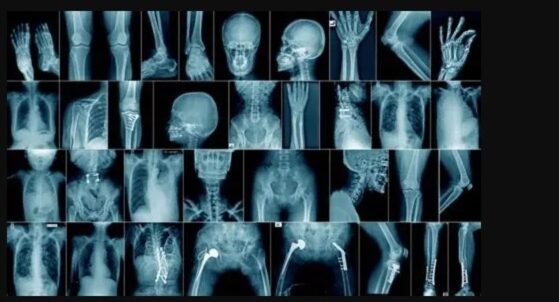

Medical X-rays produce highly detailed images of tissues and structures inside the body. If X-rays traveling through the body also pass through an X-ray detector on the other side of the patient, an image will be formed that represents the shadows formed by the objects inside the body.

The creation of a radiograph is a sophisticated process that requires precise patient positioning. This positioning ensures that the part of the body being imaged is accurately positioned between the X-ray source and the X-ray detector. When the machine is turned on, X-rays, the key players in this process, travel through the body and are absorbed in varying amounts by different tissues, depending on the radiological density of the tissues they pass through.

Radiological density, a key concept in radiography, is a measure of a material’s resistance to the passage of X-rays. It is determined by both the density and the atomic number (the number of protons in an atom’s nucleus) of the materials being imaged. For example, structures such as bone contain calcium, which has a higher atomic number than most tissues. Because of this property, bones readily absorb X-rays and, thus, produce high contrast on the X-ray detector.

As a result, bony structures stand out distinctly, appearing whiter than other tissues against the black background of a radiograph. This stark contrast is a key feature of radiographs. Conversely, X-rays pass more readily through less radiographically dense tissues, such as fat and muscle, as well as through air-filled cavities, such as the lungs. These structures appear in shades of gray on a radiograph, creating a nuanced visual representation of the body’s internal structures.